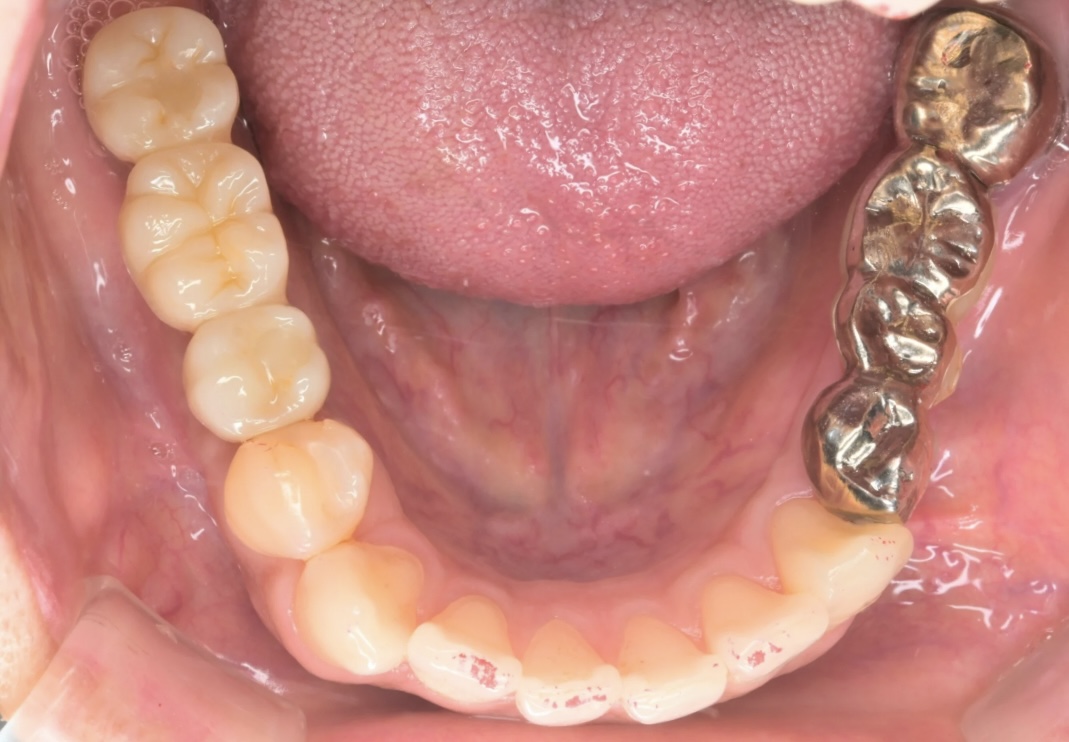

下顎奥歯にインプラントを4本埋入したケース【70代男性】

症例写真 治療詳細 年齢・性別 70代男性 患者様のお悩み 下の入れ歯が合わない。他院で何度も調整して貰ったがもうこれが限界なのかなと半ばあきらめていた。前々から気になっていたインプラントも考えてはいるがとりあえず入れ歯を調整して安定させてほしい。 治療期間 インプラント、補綴など合計で2年 リスク・副作用 術後感染、腫脹、疼痛リスク 治療費用 180万円 …